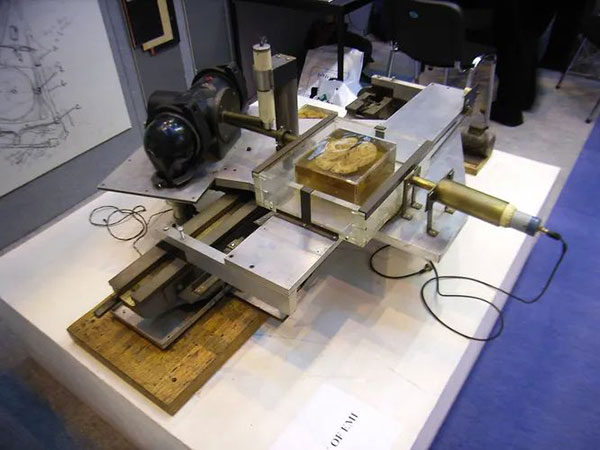

Получив начальный капитал, Хаунсфилд приступил к созданию компьютерного устройства, способного обрабатывать большое количество рентгеновских лучей для получения двумерных изображений мягких тканей живых организмов.

При производстве первого сканера использовались детали от токарного станка. Запись производилась на датчики вместо рентгеновской плёнки, что позволило сделать несколько снимков от вращающегося источника света и получить серию «срезов», демонстрирующих разную плотность тканей. Затем, сделав серию фотографий с небольшими промежутками времени, можно было получить трёхмерное изображение.

Вскоре Хаунсфилд начал экспериментировать на голове коровы, которую его коллега приобрел на кошерной бойне в восточном Лондоне. Дело в том, что при традиционном забое животных оглушали электричеством, что приводило к заполнению мозга кровью и мешало рентгенологам изучать его структуру.

Хаунсфилд с улыбкой рассказывал о том, как ехал на автобусе через весь Лондон с сумкой, полной свежего мозга телёнка, чтобы изучить регистрацию и обработку сигналов от живых тканей в лаборатории. После проведения экспериментов на мозге коров и свиней Хаунсфилд сам стал испытуемым и отсканировал свой мозг. Затем наступило время использования сканера на реальном пациенте в настоящей больнице.